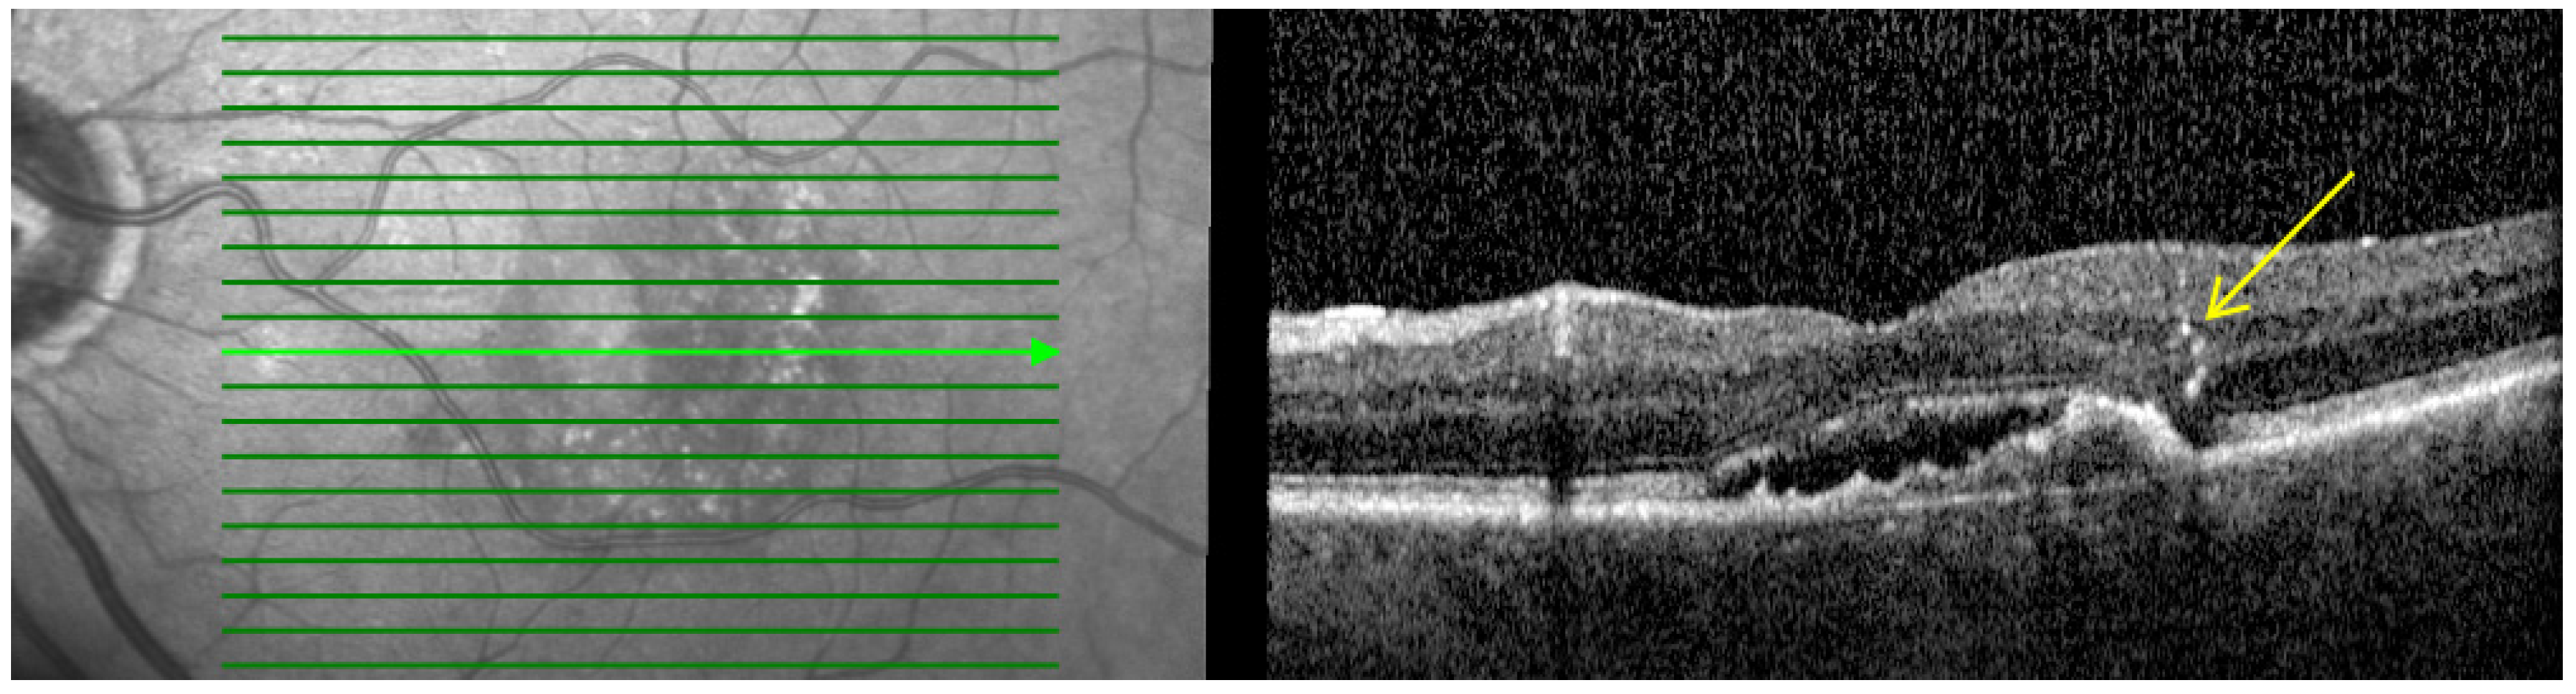

- Macular atrophy (MA): Characterized by in-lesion photoreceptor death and visual impairment and typically follows progressive atrophy and thinning of the retinal pigment epithelium (RPE) and choriocapillaris. The loss of photoreceptors can be detected by the thinning of the Henle fiber layer. This could be detected by OCT by features such as loss of the ellipsoid layer and outer limiting membrane as well as thinning of the outer nuclear layer, which together with the Henle fiber layer and photoreceptors appear as a single hyporeflective band on OCT images as shown in Figure 1 [24,25,26].